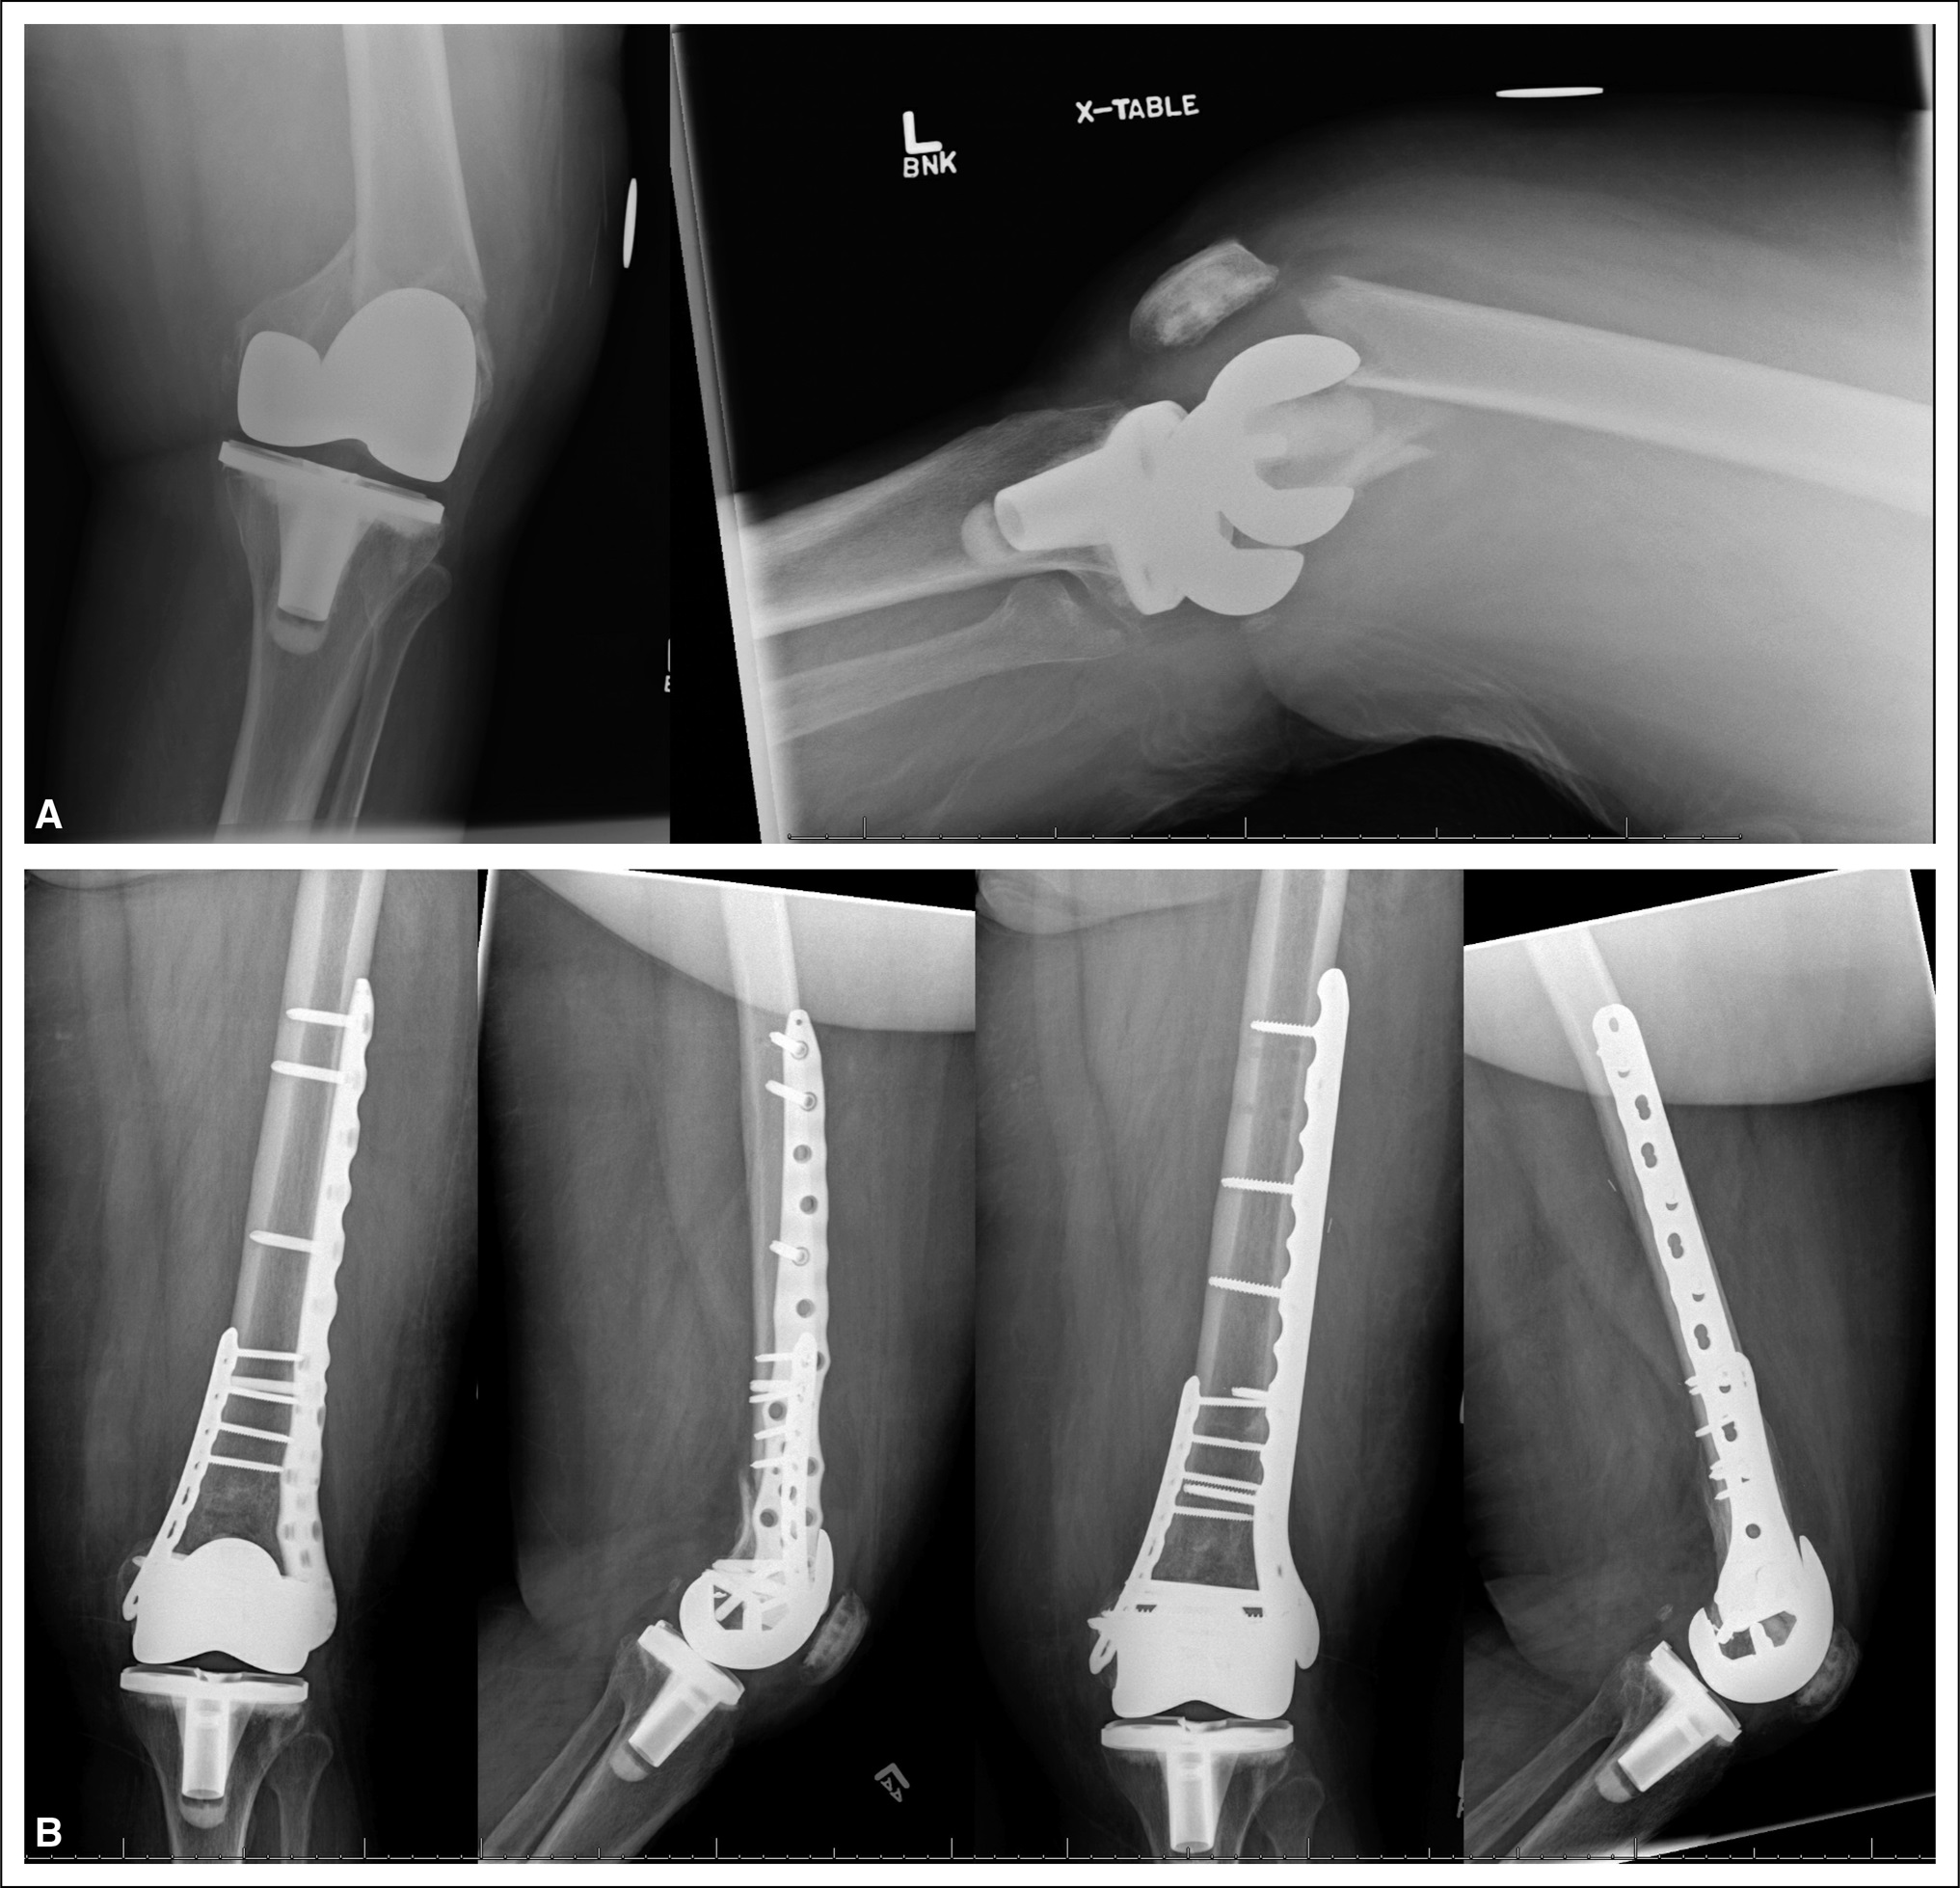

(A) This patient had a Vancouver type B1 periprosthetic femur fracture. (B) Plates were used to hold the repositioned bones together. One year after the surgery, the fracture had healed with adequate alignment, rotation, and strength.

Reproduced from Bengoa F, Neufeld M, Howard L, Masri B. Prosthetic Fractures After a Total Knee Arthroplasty. J Am Acad Orthop Surg 2023; 31[19]:e746-e759.